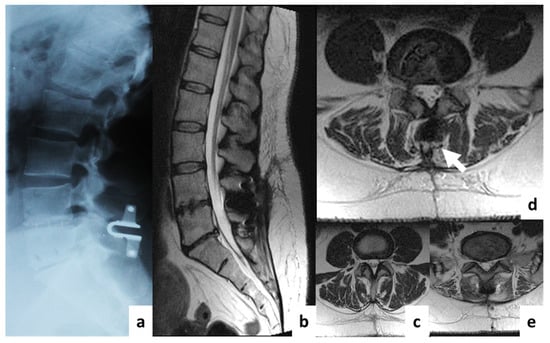

Comparison of MRI Visualization Following Minimally Invasive and Open TLIF: A Retrospective Single-Center Study

3. Results